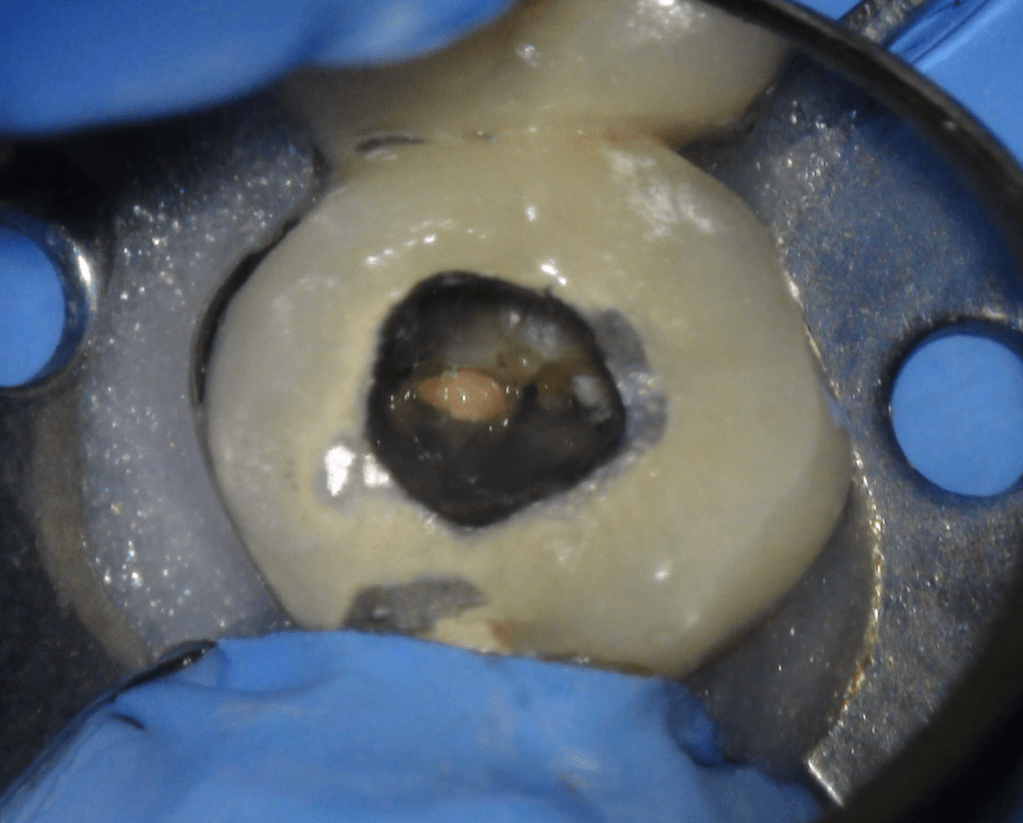

Reco pared vesticular